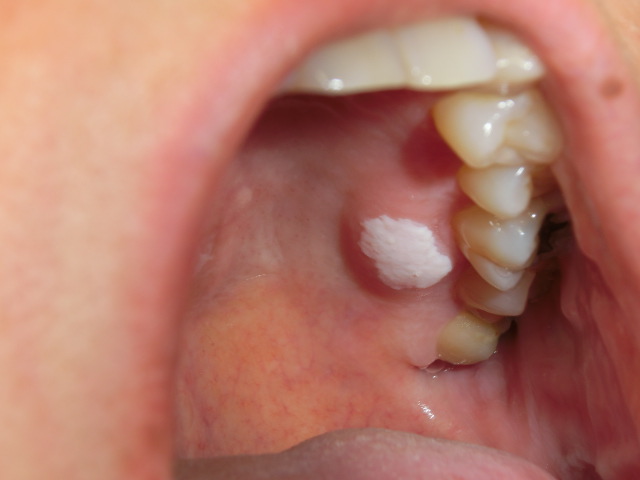

@白板症(Leukoplakia) 他のいかなる疾患としても特徴づけられない著明な白色の口腔粘膜病変。 均一型(Homogeneous)と非均一型(Non-homogenerous)に分けられる。

均一型 :平面型(flat),波状型(corrugated),ヒダ型(wrinkled),軽石様型(pumice-like)